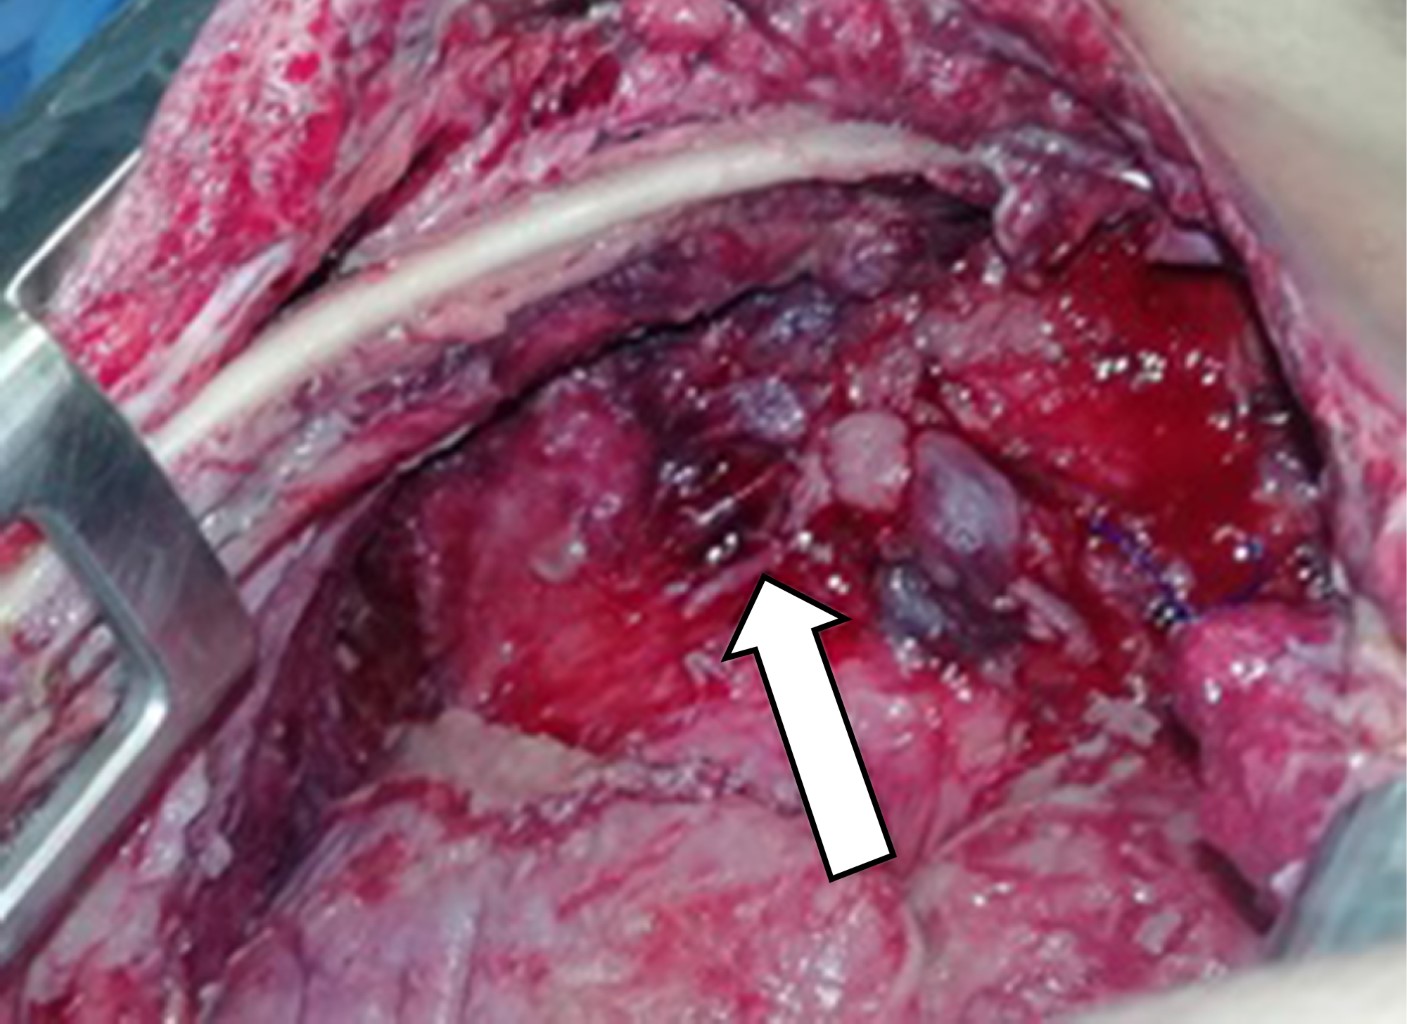

Se programó paciente para laparotomía exploratoria donde se encontró absceso subfrénico de 200 cm3, el cual se drenó. Se observó tumor dependiente de ángulo esplénico de colon de 10 por 12 cm, fistulizado hacia cavidad torácica (Figura 4). Se realizó hemicolectomía izquierda con colostomía en bolsa de Hartmann y colocación de drenaje. El diagnóstico de la pieza quirúrgica fue de adenocarcinoma moderadamente diferenciado, ulcerado y perforado que invade todas las capas de la pared con infiltración vascular y linfática.